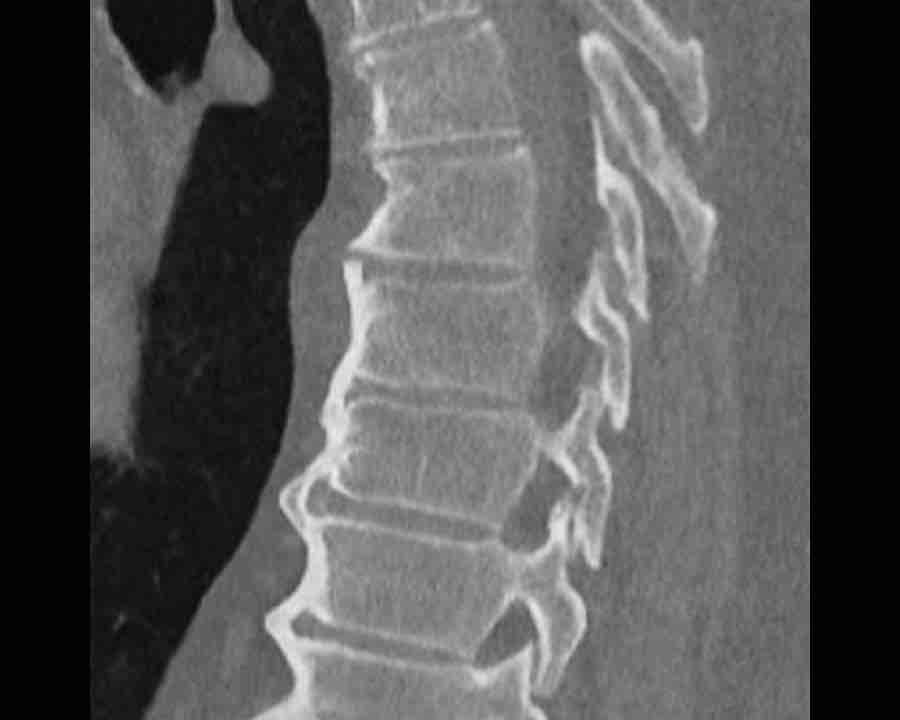

Scroll through images.

What are the findings?

Findings

- C injury? No.

- Signs of a rigid spine?

Yes, clear example of SpA so be aware of a B3 injury. - Horizontal fracture of vertebral body (white circle)

- Subtle separation anteriorly at the fracture level

Conclusion

injury type B3.